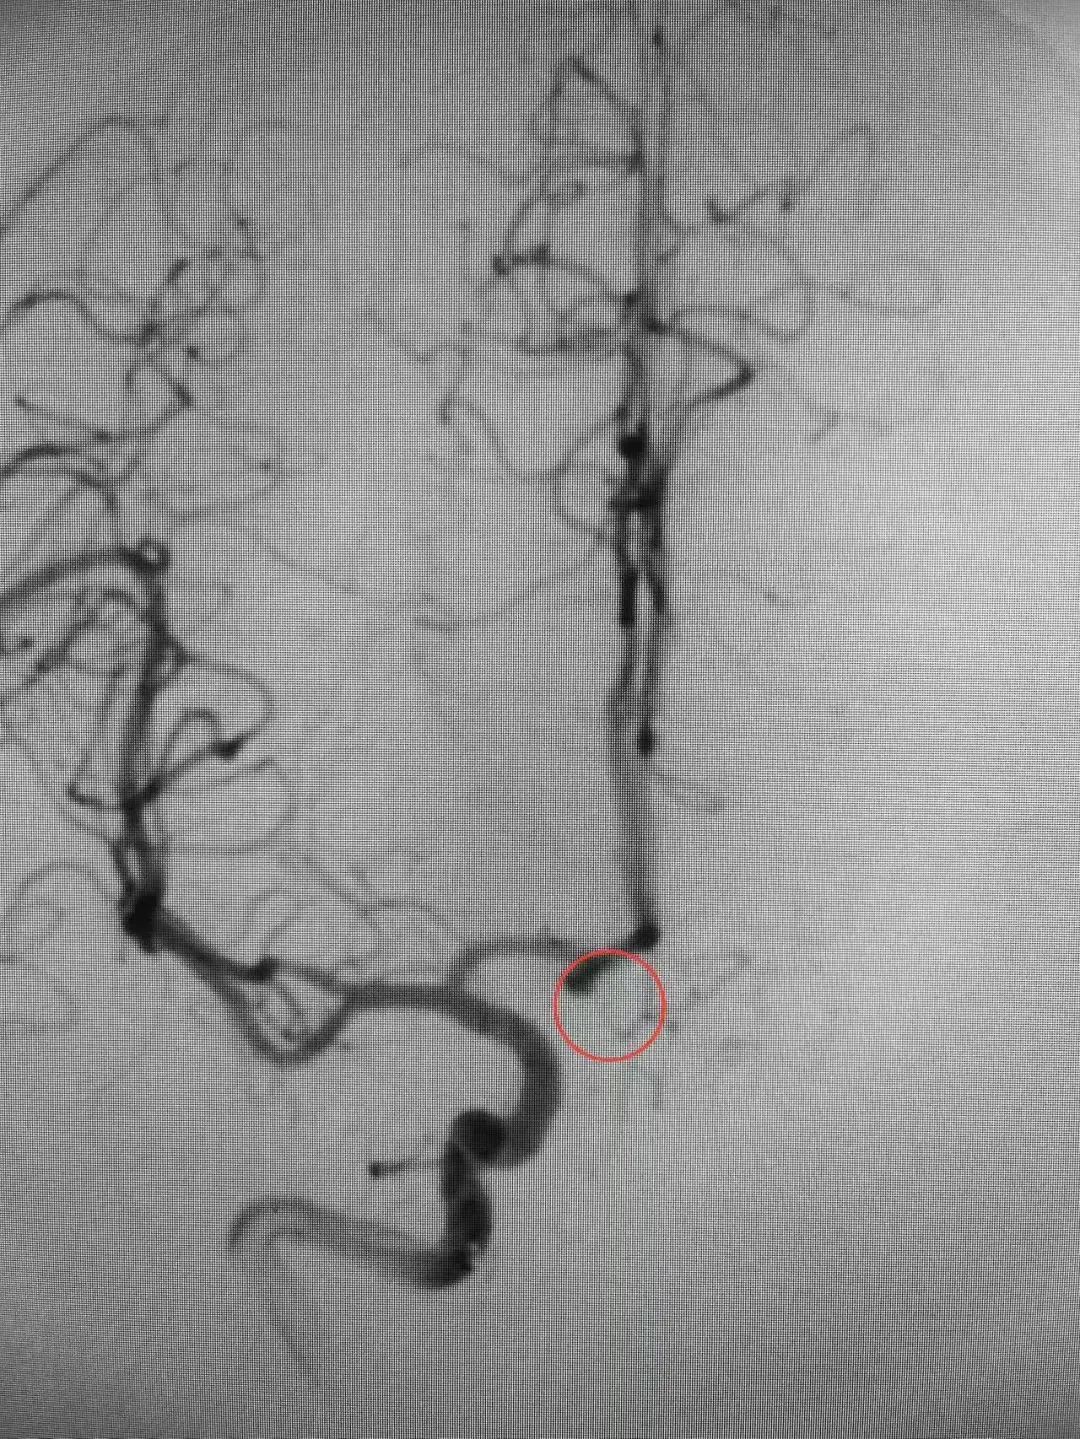

近日,殷女士在家中突发头痛,随后意识丧失,被家人送至我院急诊科。医生迅速安排颅脑CT扫描等相关检查。结果显示蛛网膜下腔出血,CTA显示前交通动脉瘤。情况紧急,我院脑病科过智伟医生考虑殷女士此次发病与动脉瘤破裂有关,前交通动脉瘤破裂死亡率高达30-40%,死亡风险高,需立即手术处理。在与殷女士家属进行充分沟通,详细解释了病情和治疗方案后,医护团队立即实施了急诊局麻下全脑血管造影+全麻颅内动脉瘤栓塞术。手术造影过程中,发现造影剂外渗,动脉瘤仍在持续出血,死亡率随之提高。医护团队沉着冷静,最终成功排除了殷女士脑中的这颗“不定时炸弹”。

△术前△ △术后△